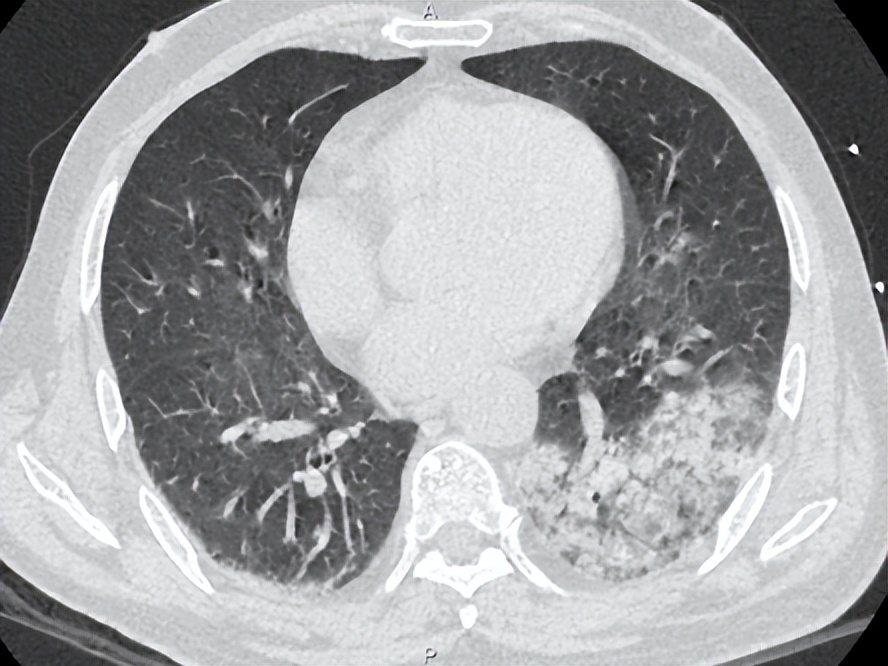

治疗后患者湿罗音减少,左肺可闻及Velcro啰音,7-6复查胸部CT如下:

考虑感染继发机化性肺炎,7.6加用泼尼松30mg po qd治疗机化性肺炎,继续多西环素0.1g bid治疗军团菌肺炎,并办理出院。

该患者的另一个临床特征是高PCT水平,据文献报道高PCT水平与需ICU治疗和高死亡率相关。 我们注意到,在病程中,PCT水平与体温未成平行下降关系,可能的原因为: 患者在入院初存在胃肠道症状和体征,包括腹泻、肠鸣音亢进。肠道作为细菌的蓄水池,此类患者可能存在肠道菌群移位。虽然没有相应的文献支持,我们在明确病原体为军团菌后,仍然将美平保留到7月2日,与多西环素重叠使用3天,直至PCT下降到安全范围。尽管在多西环素介入后, 6月30日床边胸片提示病灶较前明显增多,左肺大片浸润影,考虑到患者重症肺炎以及多个死亡相关预后因素存在,加用利福平5天联合抗军团菌。 患者在有效抗感染治疗基础上,7月6日复查胸部CT提示机化表现 ,氧合改善欠佳,给予短程激素应用,7月14日复查胸片提示病灶显著吸收。1个月后电话随访,患者原有咳嗽、气促等症状消失。